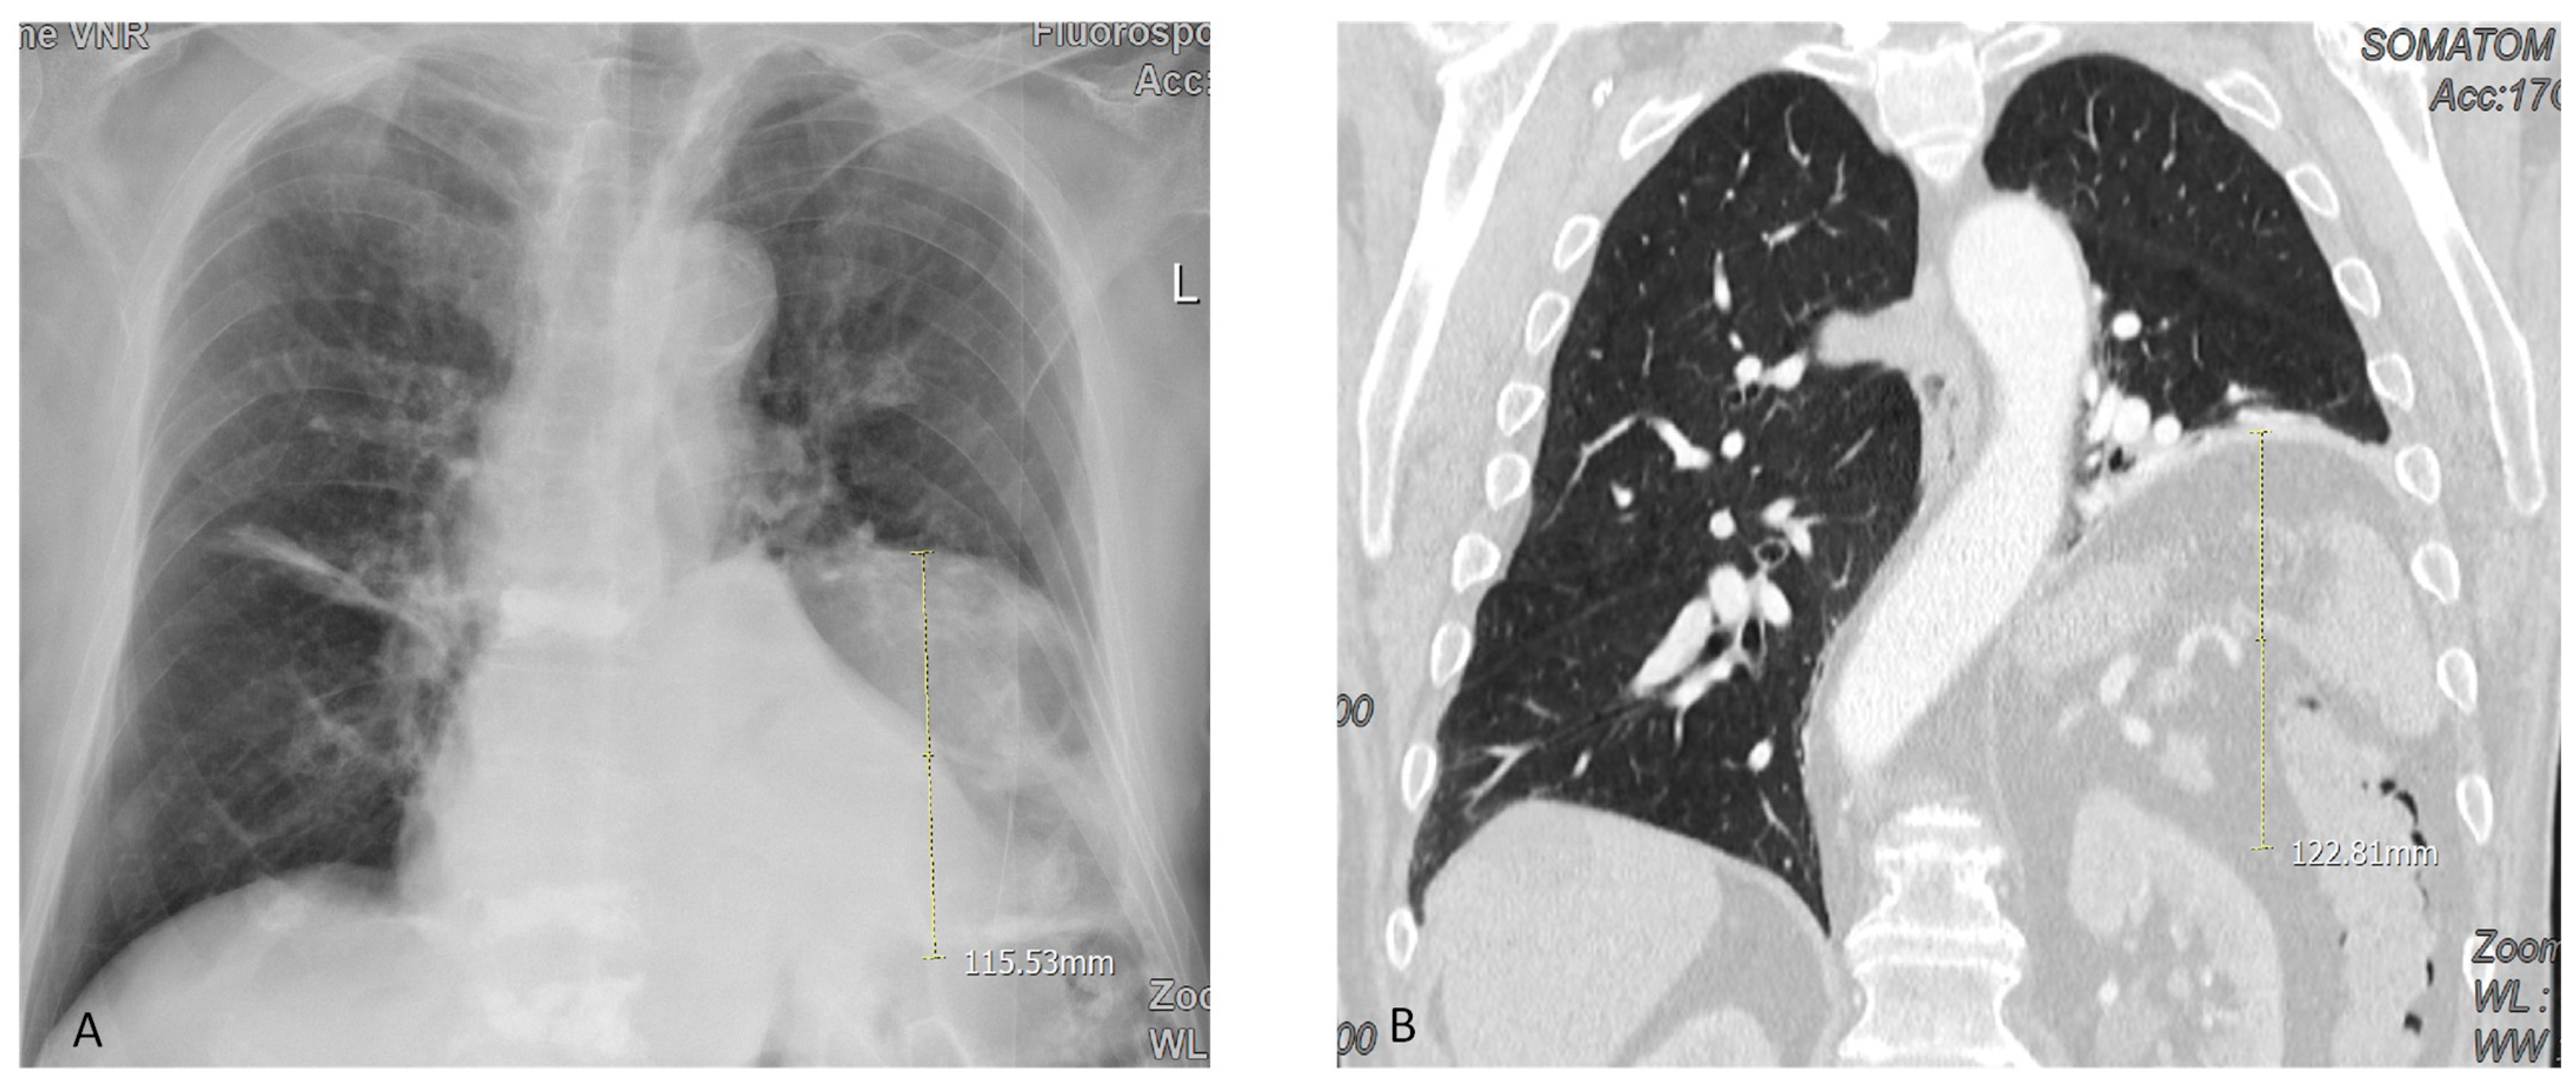

| Height of diaphragm om the X-ray (cm) | 8 ± 4 | 0.018 |

| Position of the plicated diaphragm on X-ray | 0.001 | ||

| Excellent (diaphragm reaches its original position) | 125 | 93 | |

| Satisfactory (2–3 cm higher than the original position) | 9 | 7 | |